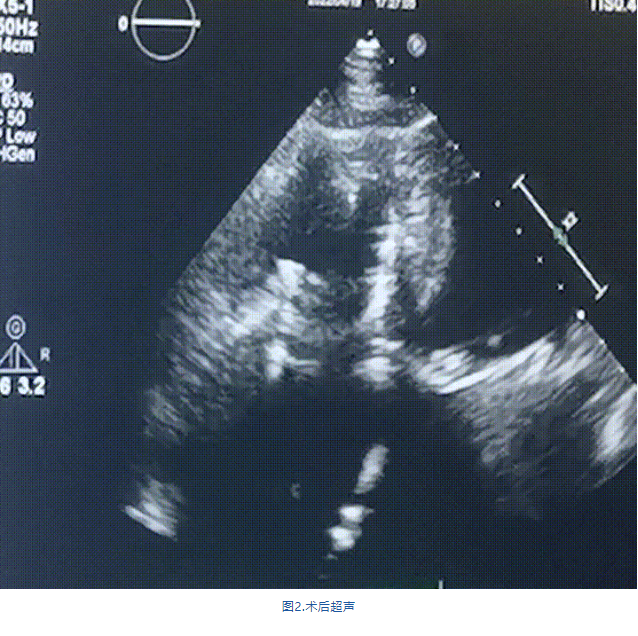

此次手術(shù)在全麻下進(jìn)行,采用經(jīng)右側(cè)頸靜脈入路。術(shù)中在經(jīng)食道超聲和DSA的指引下多個(gè)維度精細(xì)調(diào)整輸送器角度,在達(dá)到正確位置后,逐步釋放瓣膜錨定裝置和盤片,最終完成瓣膜植入。術(shù)后患者右房壓明顯下降,術(shù)后超聲提示人工三尖瓣同軸性良好,瓣架固定牢靠,無(wú)反流和瓣周漏,血壓術(shù)后即刻上升20mmHg左右,手術(shù)后監(jiān)護(hù)室順利拔除氣管插管,3天后恢復(fù)良好,予以出院。